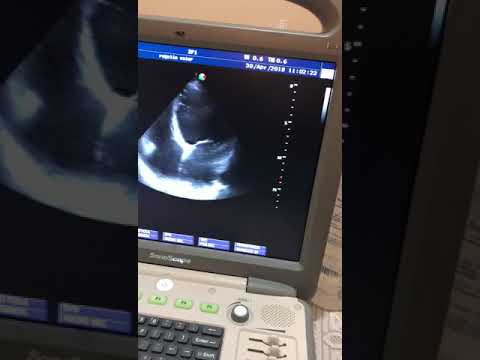

Ecocardiograma de paciente con hipertrigliceridemia severa, dilatación leve del VI, movimiento paradojal del séptum por BCRI. Dr. Luciano Pereira. Ciudad del Este. Paraguay